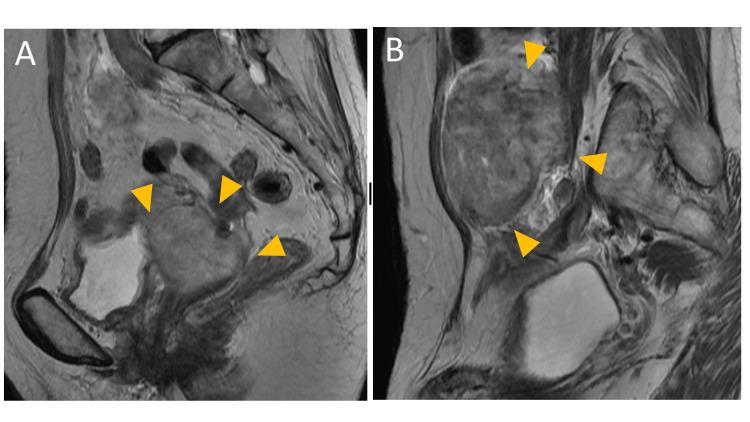

Uterine leiomyomas commonly reduce naturally after menopause. We report a rare case of metastasizing leiomyoma that grew after surgical menopause. A 68-year-old woman suffered from pelvic and lung masses without clinical symptoms. Nineteen years ago, she underwent a total hysterectomy and bilateral adnexectomy for multiple uterine myomas and bilateral endometriotic cysts. She has since been regularly prescribed conjugated estrogens. Surgery was scheduled in order to rule out malignancy; abdominal masses resection and thoracoscopic left partial pulmonary resection (S3, S4, S10) were performed. The histological diagnosis was leiomyoma in both abdominal and lung masses, and there was no evidence of gene mutations, which suggested that leiomyosarcoma was indicated. This case may indicate that hormone replacement was augmented via derived nutrient vessels after a surgical ovarian absence.

子宫平滑肌瘤通常在绝经后自然缩小。我们报告一例罕见的转移性平滑肌瘤,其在手术绝经后仍生长。一名68岁女性患有盆腔和肺部肿块但无临床症状。19年前,她因多发性子宫肌瘤和双侧子宫内膜异位囊肿接受了全子宫切除术和双侧附件切除术。此后她一直定期服用结合雌激素。为排除恶性肿瘤安排了手术;进行了腹部肿块切除术和胸腔镜下左肺部分切除术(S3、S4、S10)。组织学诊断为腹部和肺部肿块均为平滑肌瘤,且没有基因突变的证据,提示为平滑肌肉瘤。该病例可能表明,手术切除卵巢后,激素替代通过衍生的营养血管增强。